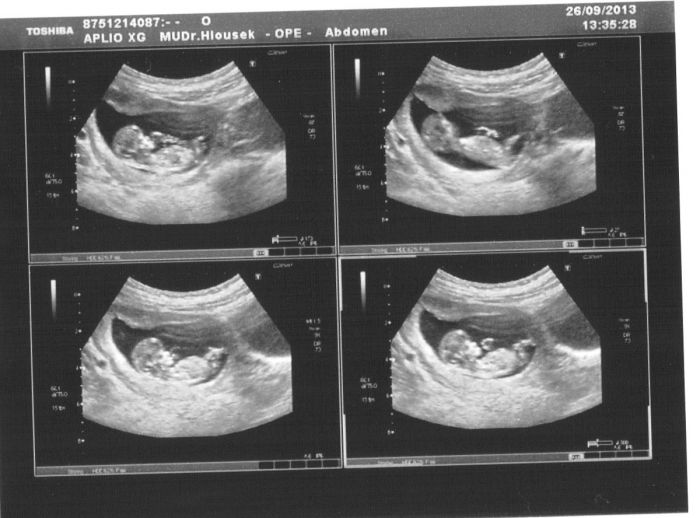

Ahoj holky, včera jsem byla na tom 2. screeningu. Dle pana doktora vše celkem odpovídá, jen si mě pozval na kontrolu za 14 dní, protože malému občas vynechávalo srdíčko (arytmie). Tvrdil, ale ať zachovám klid, že se to vývojem může spravit. To slovo může, mě ale stejně rozhodilo. Jinak malému zkontroloval co se dalo. Kompletně proměřil mozek, obvod hlavičky je něco kolem 18 cm, zkontroloval ručičky, nožičky, proměřil délku stehenní kosti, ukázal nám kde má oči, obě ledviny. Ukázal, že fungují. Zkontroloval průtok pupečníkem, chodidla. Řekl, že má založené zuby. Našel pindíka. Placenta je na zadní straně, plodové vody dostatek. Váhu podle všech měření odhaduje na 365 g. Dnes jsem dle UZ 21 tt. Tak teď se budu jen modlit za to srdíčko. Všem vám přeji, jen a jen dobré zprávy.